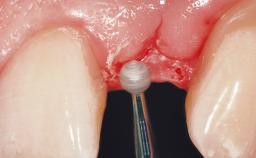

A 39-year-old male patient presented with a chief complaint of discomfort and gingival discoloration around his maxillary left central incisor. He was in good general health and was a non-smoker. His past dental history was significant because of the traumatic fracture of tooth 21 in a sporting accident at age 13. Initial dental treatment included endodontic therapy and a full-coverage restoration. The patient became symptomatic 5 years later, when structural failure of the tooth resulted in the dislodgment of the crown. Endodontic retreatment, apical surgery, and post-and-core restoration were performed.

| Bone Augmentation | Horizontal|Staged |

| Soft Tissue Grafting | Simultaneous |